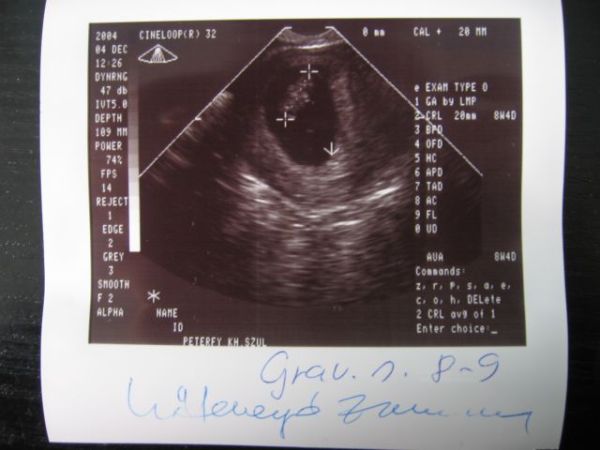

Most magánredelőbe egy nagyon kedves, segítőkész dokibácsihoz járunk. Már az első vizsgálatnál behívta a férjemet és együtt néztük meg UH-n mazsolát.